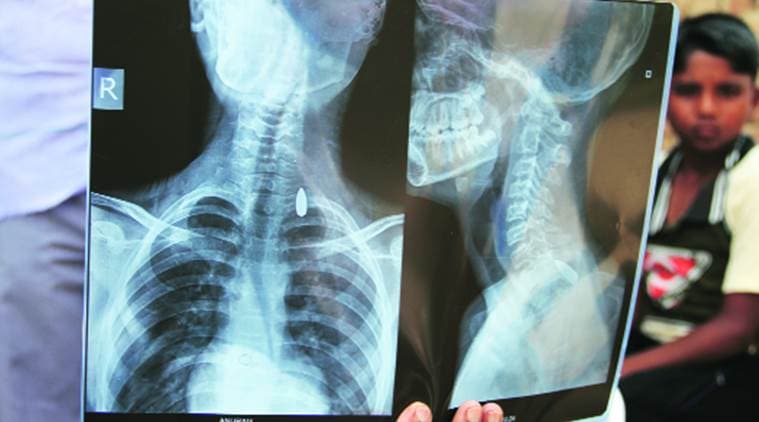

Ismailpur, Ismailpur shooting, Air Force, Air Force bullets, Tilpat firing range, delhi news X-rays of Anurag Singh, 13, show the bullet. Gajendra Yadav

Family members of the two children and the man hit by bullets have accused Safdarjung hospital of not treating them properly and discharging them in a hurry. “The bullet which is still stuck in Anurag’s neck will never be taken out as the family has no money for his operation,” said the boy’s uncle.

Anurag’s uncle Ajit said doctors at Safdarjung hospital discharged him without treating him properly. “His bullet is inside and doctors told us it will take a huge amount of money for operation. His father is a driver… how can he arrange a big amount?” Anurag has written to Prime Minister Narendra Modi seeking help from him in the matter.

According to doctors at the hospital, operating on Anurag initially would have been risky, with chances of critical nerves in his body getting affected and hampering movement. “He was admitted for 4-5 days, given all necessary emergency treatment and evaluated properly. He has also been called for follow-up. Disturbing the bullet immediately after injury could have affected critical nerves due to its position. We are waiting to see his recovery first,” said a doctor.